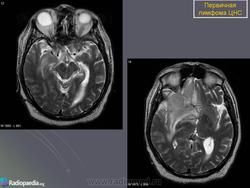

Первичные лимфомы ЦНС. Вс, 22/05/2011 - 21:45 #1 Катенёв Валенти... Не на сайте Был на сайте: 7 лет 5 месяцев назад Зарегистрирован: 22.03.2008 - 22:15 Публикации: 54876 Продолжение.Приложения:

Продолжение.